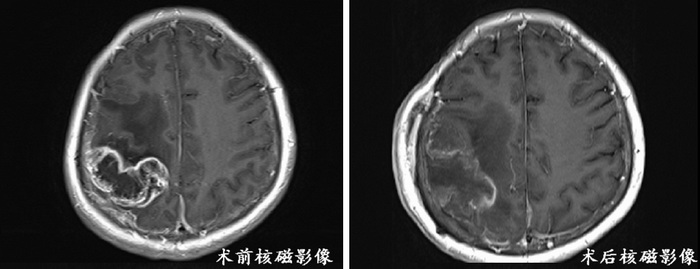

脑功能区胶质瘤是生长位置较为特殊的一种胶质瘤,指的是发生于脑功能区(即与语言、感觉、运动、听觉、视觉等功能密切相关的皮质及皮质下通路区域)的胶质瘤,这些功能区如若受到损伤将会引发永久性神经功能障碍。因此,对于脑功能区胶质瘤,行手术治疗时需要保护好基本神经功能,以免造成功能障碍,手术难度非常高,目前国内外最先进的手术方式是应用神经导航技术引导切除功能区胶质瘤,在术中应用磁共振功能神经导航技术对于准确评估术中肿瘤切除程度,最大化切除肿瘤,避免肿瘤周围血管、神经及语言运动功能区受损具有重大意义。最近,我院神经外科应用神经导航技术成功开展了功能区巨大胶质瘤手术。

66岁的刘阿姨,三个月前开始出现左侧肢体及面部麻木症状,来到我院神经外科门诊就诊。张洪兵主任详细了解了病史,为刘阿姨完善了头CT检查后发现在患者右侧功能区有占位性病变。为了能够得到快速精准的治疗,医学影像中心很快为刘阿姨完善了头MRI+C、头MRS、头DTI等多模态影像检查,考虑属于功能区高级别巨大胶质瘤可能性大,且肿瘤位置特殊,如果采用传统手术无疑会导致左侧肢体偏瘫、偏身感觉障碍等灾难性后果。神经外科立即组织病例讨论,根据患者病史、查体及辅助检查,诊断为高级别胶质瘤,因其体积巨大、生长迅速、恶性程度高,手术指征明确。但由于瘤体位于功能区,术后出现偏瘫、感觉障碍可能性极大。切,患者很可能就瘫痪;不切,这种肿瘤的恶性生长很快就会出现脑疝,危及生命,作为医者,神经外科医生面临着进退两难的境地。根据国内外发表的文献,团队经过充分讨论后一致认为:手术一定要做,但要在神经导航引导下辅助定位病灶及功能区,根据患者神经纤维分布情况避开重要神经传导束进行手术切除肿瘤。立即组织了影像医学科、肿瘤科、手术室、麻醉科、病理科多学科会诊,以MDT的模式共同为刘女士术前、术中及术后的病情与治疗进行了综合评估;并与神经导航专家共同制定手术计划,进行手术模拟演练,讨论相关风险与手术细节。

术后一周,刘女士肢体不但没有瘫痪,而且肌力还有所好转,病理证实为胶质母细胞瘤,随后为她安排了标准的术后放化疗方案,术后10天康复出院,相信经过一段时间的治疗与康复锻炼,刘女士能够恢复正常的生活。